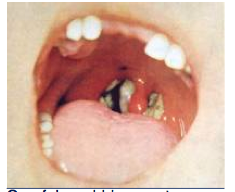

What would you expect to culture from these lesions?

C. diphtheria

(produces pseudomembrane of pharynx, tonsils, nose)